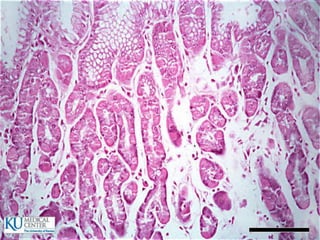

Intestino delgado  720cm de longitud  Duodeno: 20 cm  Yeyuno  Íleon

Especializaciones superficiales de lamucosa  Pliegues circulares (válvulas de Kerckring)  Vellosidades y criptas  Microvellosidades  Tipos de glándulas:  Intestinales  Submucosas (Brunner)  Situadas fuera del tubo digestivo

Intestino delgado  Epitelio: Células cilíndricas  Células de Paneth  Células caliciformes  Células enteroendócrinas